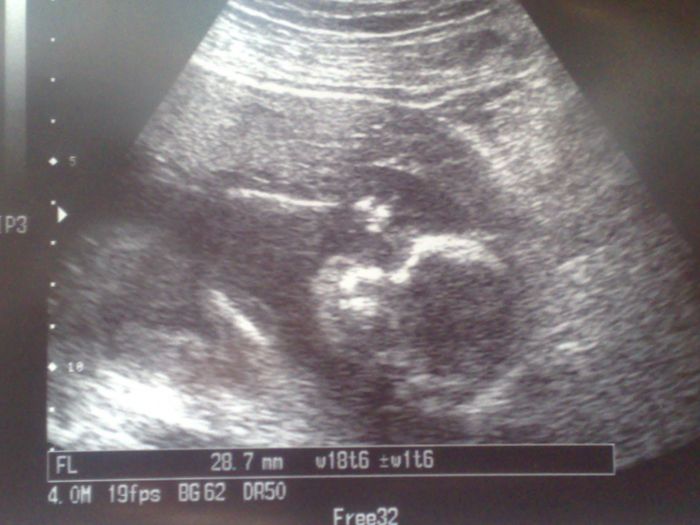

19+4

my jsme byli s manželem minulý týden na velkém UZ a pan doktor nám řekl že budeme mít holčičku Andělku:) Manžel je šťastný moc si holčičku přál:) Už od včerejška cítím v bříšku bublinky a takový jako vlnění jennevím jestli to jsou pohyby nebo střeva ale je tojiný než třeva:) Takový jemný :) Vždycky mam kránsý pocit když to cítím:)